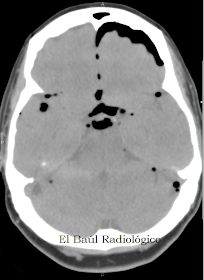

Las siguientes imágenes corresponden a una paciente de 76 años que acudió a Urgencias por un cuadro clínico de rinorrea persistente de varias semanas de

evolución. Se realizó TAC craneoencefálica que puso de manifiesto neumoencéfalo frontal y pequeñas burbujas de aire dispersas por el espacio subaracnoideo de las cisternas basales y de los surcos de la convexidad cerebral. No refería antecedente traumático ni infeccioso.

FIGURA 2) Neumocéfalo subdural frontal (flecha amarilla) y neumocéfalo subaracnoideo en la cisternas de los ángulos pontocerebelosos y en la supraselar (Flechas rojas)